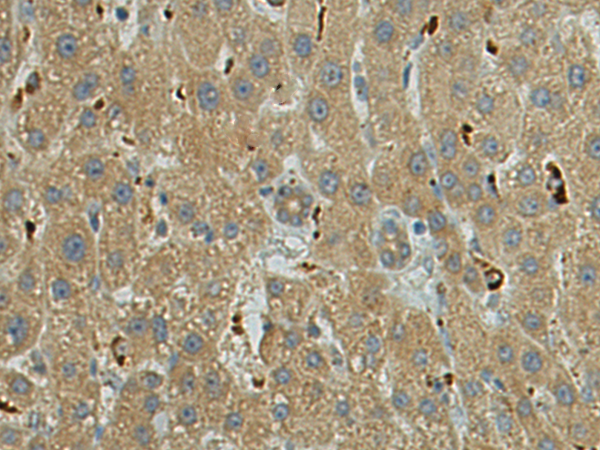

分类: 科研抗体货号: P05595别名:应用: WB,IHC反应种属: Human, Mouse